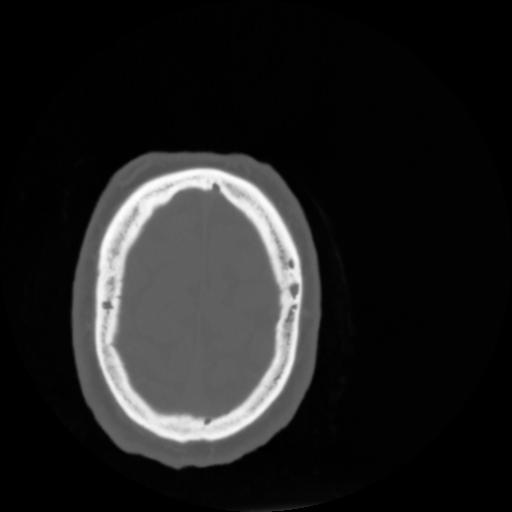

4 CEREBRO,,Vol,0.5,CEREBRO,,